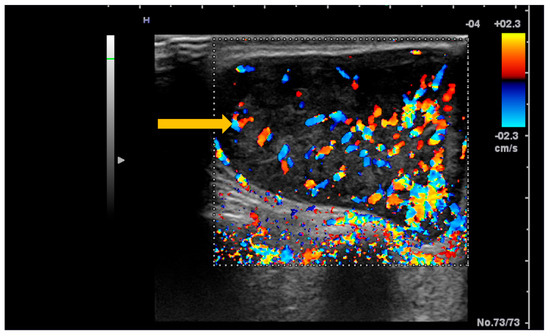

The Role of Imaging Techniques in the Evaluation of Extraglandular Manifestations in Patients with Sjögren’s Syndrome

Sjögren’s syndrome is a chronic autoimmune disease marked by lymphocytic infiltration of the exocrine glands and the development of sicca symptoms, yet some patients also develop extraglandular involvement. Imaging has become relevant for describing these systemic features and supporting clinical assessment. This review discusses the roles of ultrasonography, elastography, computed tomography, and magnetic resonance imaging in evaluating multisystem disease associated with Sjögren’s syndrome. Ultrasonography and elastography help assess muscular involvement by showing changes in echogenicity and stiffness that reflect inflammation and later tissue remodeling. In joints, ultrasound can detect synovitis, tenosynovitis, and early erosive changes, including abnormalities not yet evident on examination. Pulmonary disease, most often with interstitial lung involvement, is best evaluated with high-resolution computed tomography, which remains the most reliable imaging modality for distinguishing interstitial patterns. Magnetic resonance imaging is valuable in assessing neurological complications. It can reveal ischemic and demyelinating lesions, neuromyelitis optica spectrum features, or pseudotumoral appearances. Imaging is also essential for detecting lymphoproliferative complications, for which ultrasound and magnetic resonance imaging can reveal characteristic structural and diffusion-weighted imaging findings. When combined with clinical and laboratory information, these imaging methods improve early recognition of systemic involvement and support accurate monitoring of disease progression in Sjögren’s syndrome. Full article